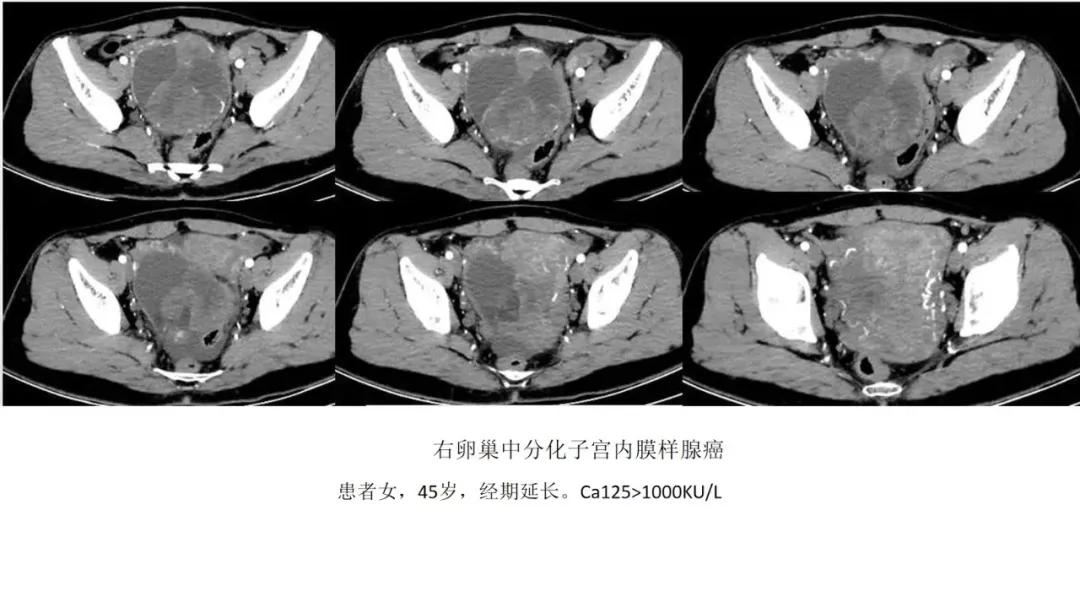

- 子宫内膜样癌与透明细胞肿瘤临床、影像表现比较类似,是微差别的上皮双胞胎

- 伴子宫内膜增厚:性索间质性肿瘤(颗粒为主)、子宫内膜样癌、透明细胞肿瘤

- 囊实性伴壁结节:透明细胞肿瘤、子宫内膜样癌